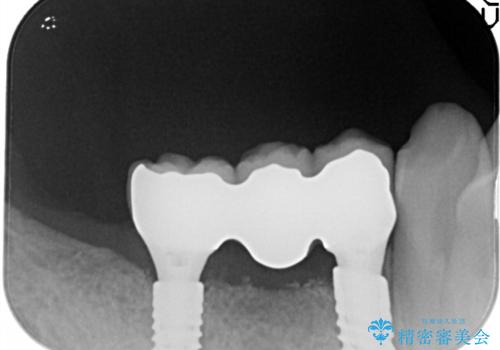

奥歯がなくなり咬めない インプラント治療による咬み合わせの回復

右の上下の歯を抜歯してインプラントを埋入して、かぶせ物を装着する計画としました。

右側のかみ合わせを回復するには、インプラントか入れ歯のどちらかの方法で治療する必要があました。

治療方法について十分な説明を行い、インプラント治療を選択されました。